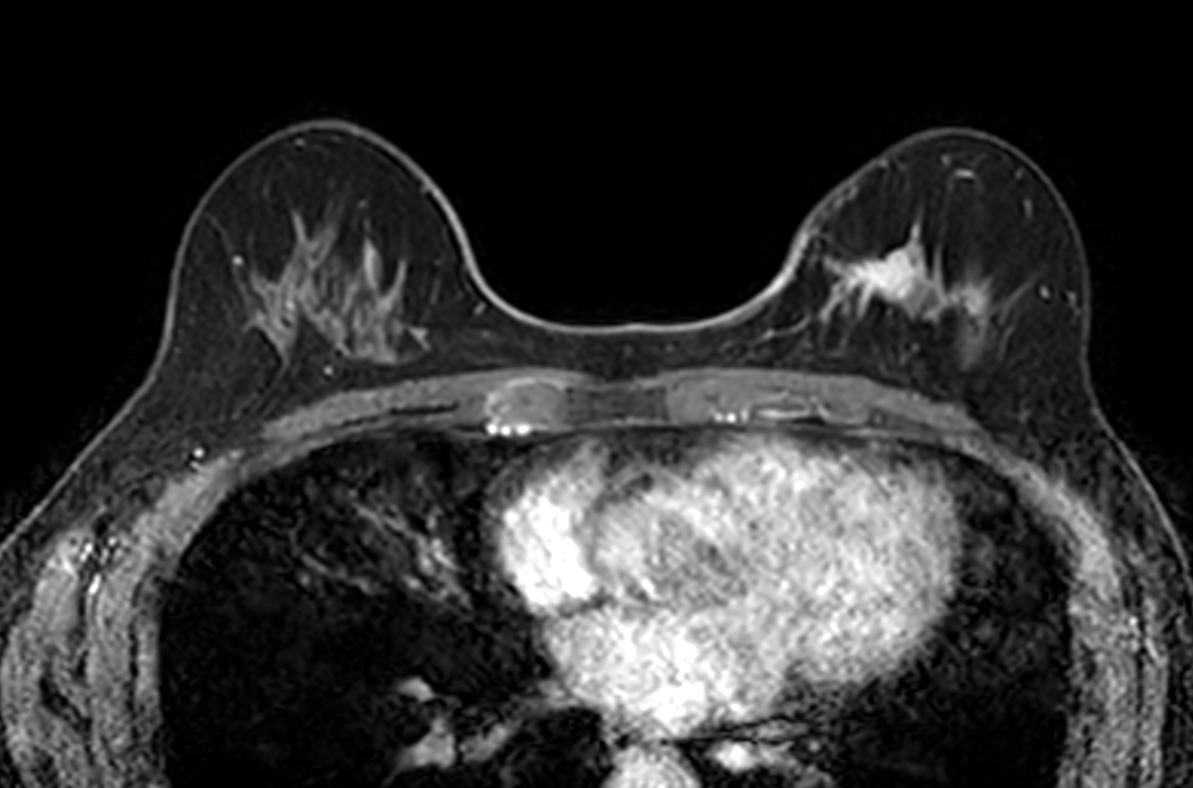

Axial dyn eTHRIVE plus gado

-